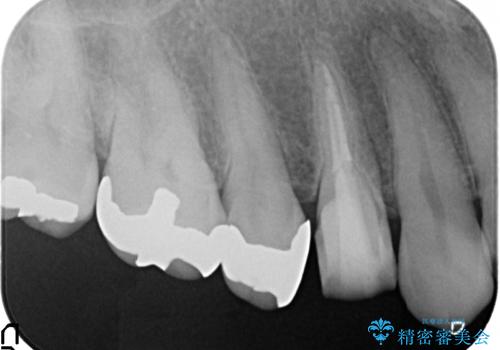

- 右上4番目の歯がなにもしなくてもズキズキ痛むといらっしゃった方の症例です。

検査の結果持続痛も認めたため、虫歯除去後根管治療を行いました。

その後オールセラミッククラウン(エクセレント)による補綴を行いました。